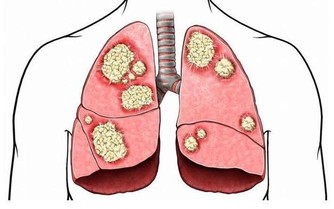

- 監控功能:及時識別和清除染色體畸變或基因突變的細胞,防止癌瘤的發生。

7、經常咳嗽,或支氣管、肺部等發炎;

硒是人體不可或缺的微量元素,幾乎存在於所有免疫細胞中。一旦缺乏,會導致免疫力下降,甚至增加癌症風險。